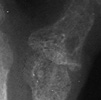

RA

- ++

Rheumatoid Arthritis

++

+++